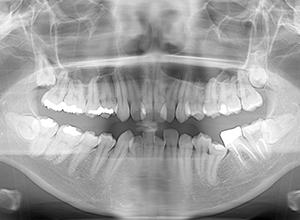

FP・IOP

X-Ray

X-Ray所見

セファロ所見 下顎骨体部は小さくないものの下顎枝は短く、下顎頭は後方に位置付き中顔面高は高いため、下顎はクロックワイズローテーションしており、前後的にはII級の骨格形態を示していた。

パノラマ所見 上下顎両側第三大臼歯は埋伏していた。下顎右側大臼歯から犬歯まで近心傾斜し、左側においては左下5を境に大臼歯は近心傾斜、近心の歯は遠心方向へ傾斜が認められた。